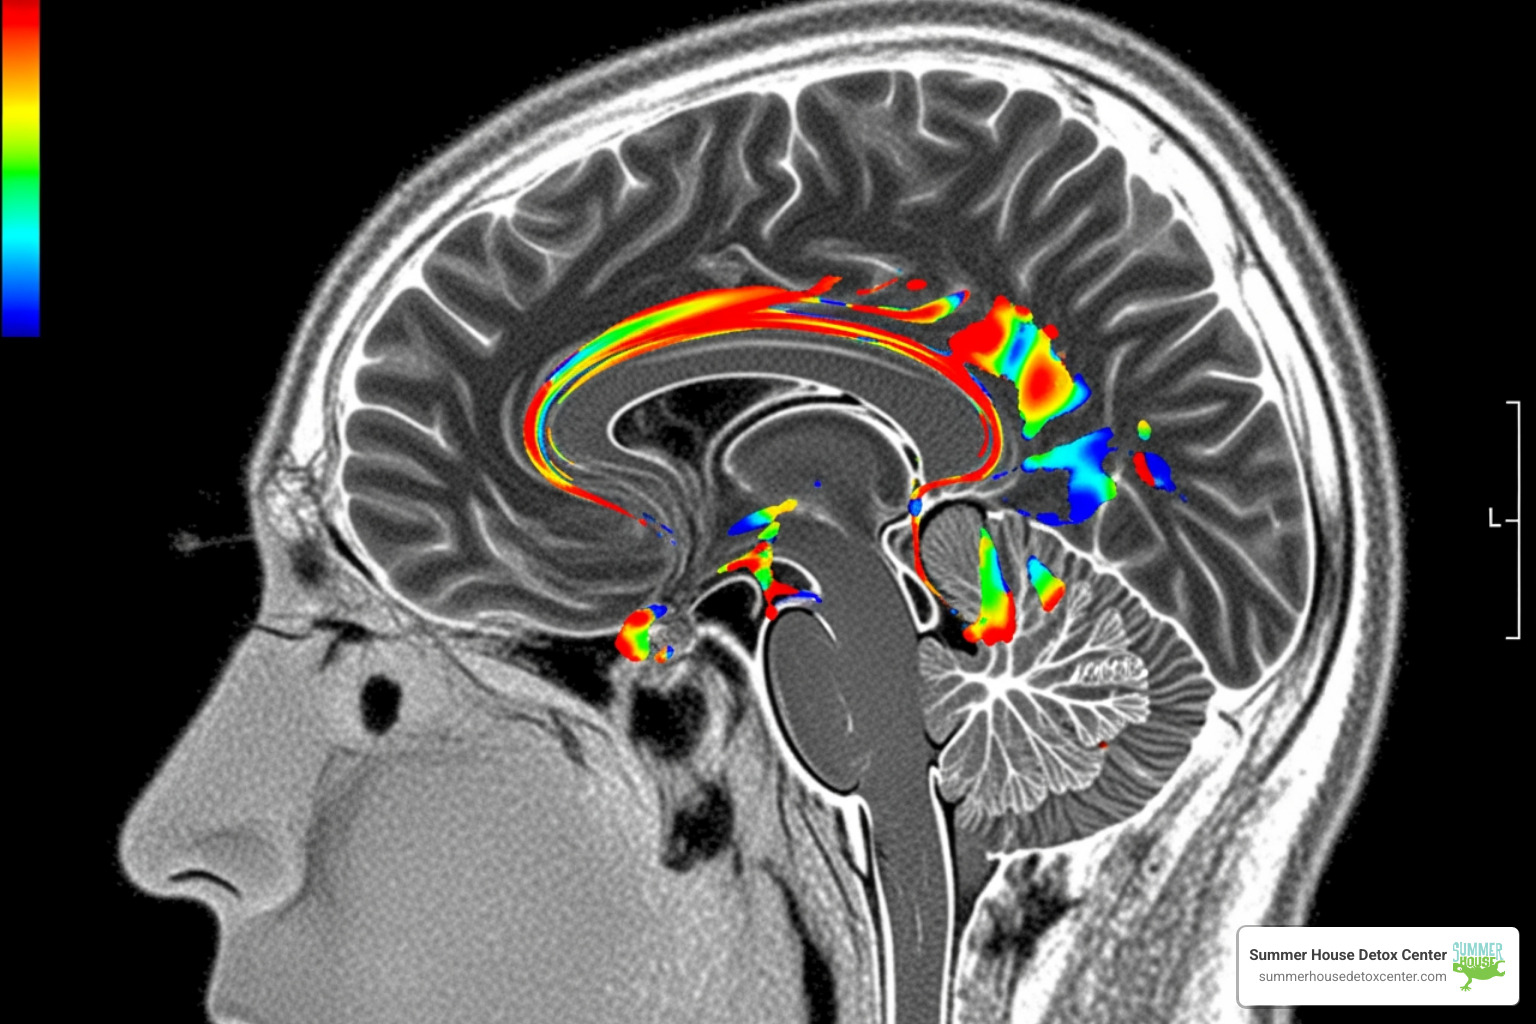

At its core, naltrexone for alcohol is an opioid antagonist. Now, before you scratch your head and wonder what opioids have to do with alcohol, let us explain. When you drink alcohol, particularly in larger quantities, it triggers the release of endorphins in your brain. These endorphins are the body’s natural opioids, and they bind to opioid receptors, producing the “feel-good” sensation or euphoria that many people associate with drinking. Over time, this pleasurable response reinforces the act of drinking, creating a powerful cycle of cravings and dependence.

Naltrexone steps in by binding to and blocking these opioid receptors. When the receptors are occupied by naltrexone, the endorphins released by alcohol have nowhere to go. As a result, alcohol can no longer produce the same euphoric or rewarding effects. Imagine turning down the volume on your favorite song—it’s still playing, but it doesn’t have the same impact. That’s essentially what naltrexone does to alcohol’s appeal. By reducing this “reward,” naltrexone helps to:

Naltrexone isn’t a cure for alcohol use disorder (AUD), because AUD is a complex, chronic brain disease. Instead, medication is one powerful tool in a comprehensive treatment plan. Naltrexone helps modify the hypothalamic-pituitary-adrenal (HPA) axis, the body’s central stress response system, which becomes dysregulated by chronic alcohol use and contributes to cravings. By interrupting the brain’s reward and stress cycles, it gives you the leverage to gain better control over your drinking and engage more effectively in therapy. For those concerned about how alcohol affects their brain, learning more about Does Alcohol Addiction Change the Way the Brain Works? can provide additional insights.